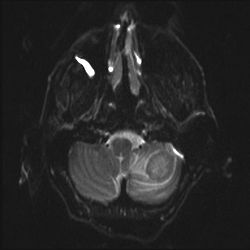

Hvorledes ser en cystisk tumor ud på diffusionsvægtet MR?

CT DWI ADC

En cystisk tumor er mørk på DWI og lys på ADC